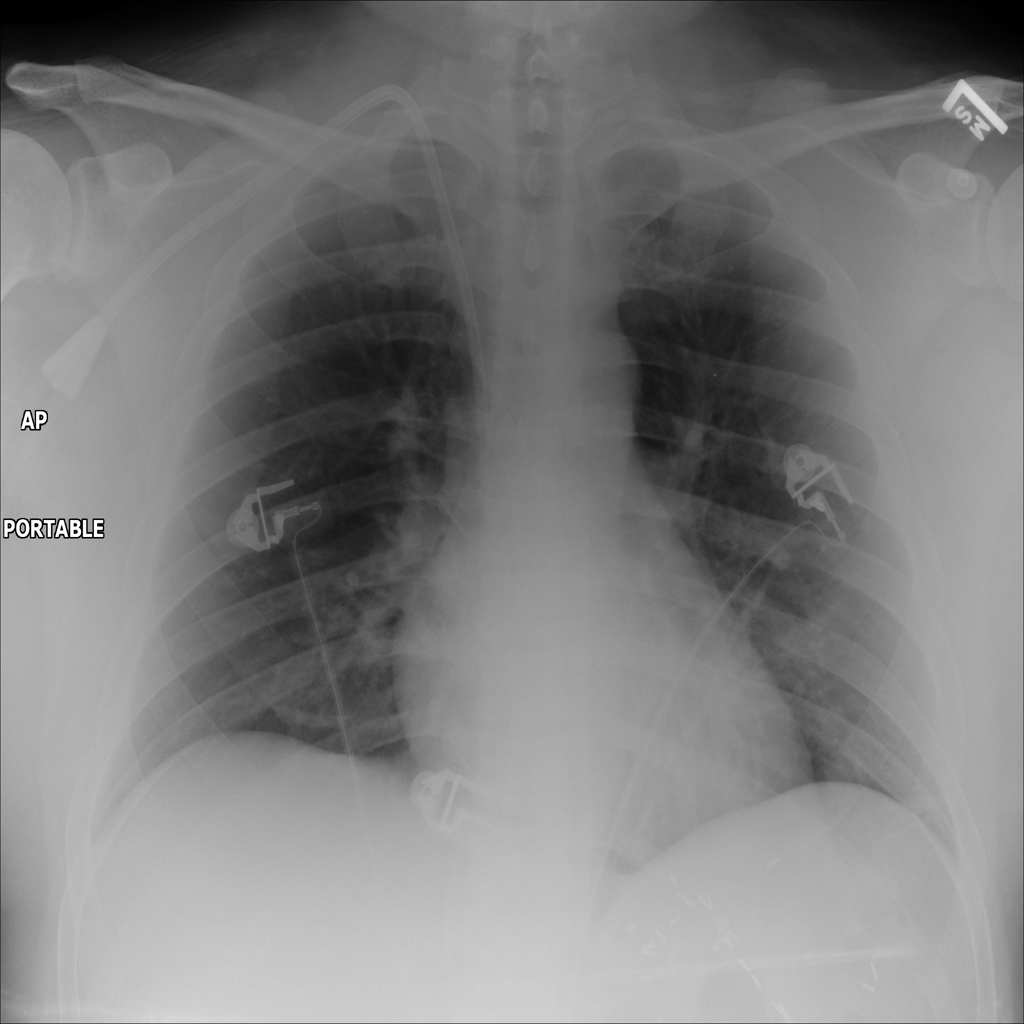

PAT-B625 · IMG-008Atelectasis

PAT-B625 · IMG-008

AP